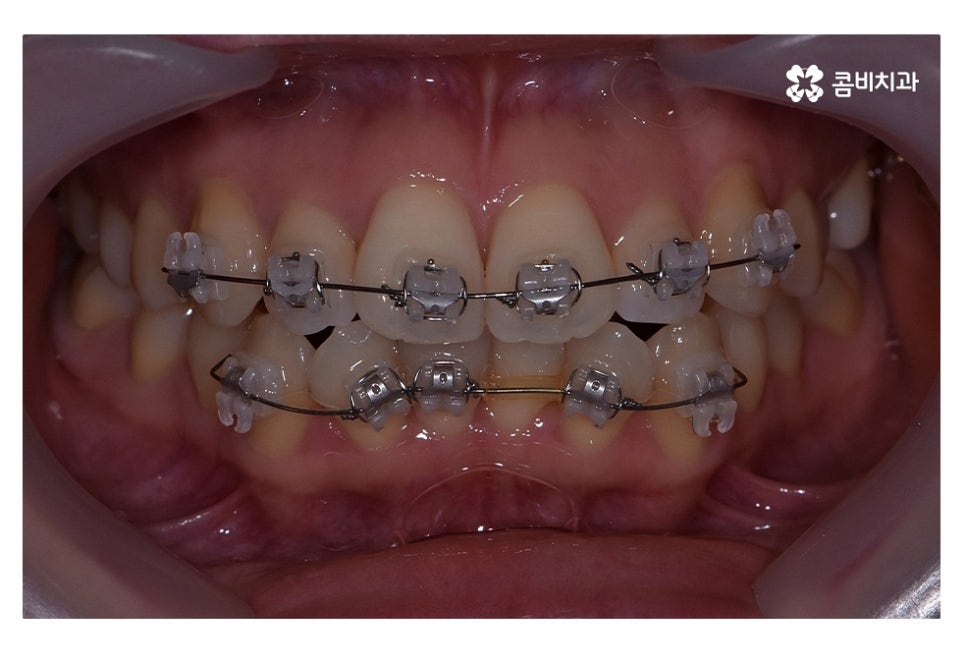

위 사진은 치료가 시작되고 약 5개월 정도가 지난 후의 모습인데

치아부분교정으로도 치열이 빠르게 가지런해진 모습을 볼 수 있어요.